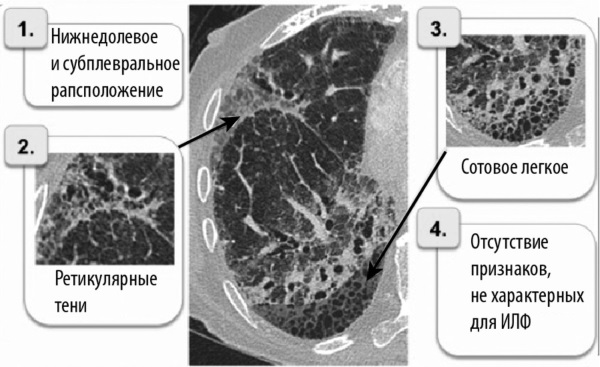

- Компьютерная томография — дополняет рентгенографию, позволяет сделать более детальные и понятные снимки для изучения.

- Рентгенография —врач по снимкам изучает уплотнения и очаги фиброза.